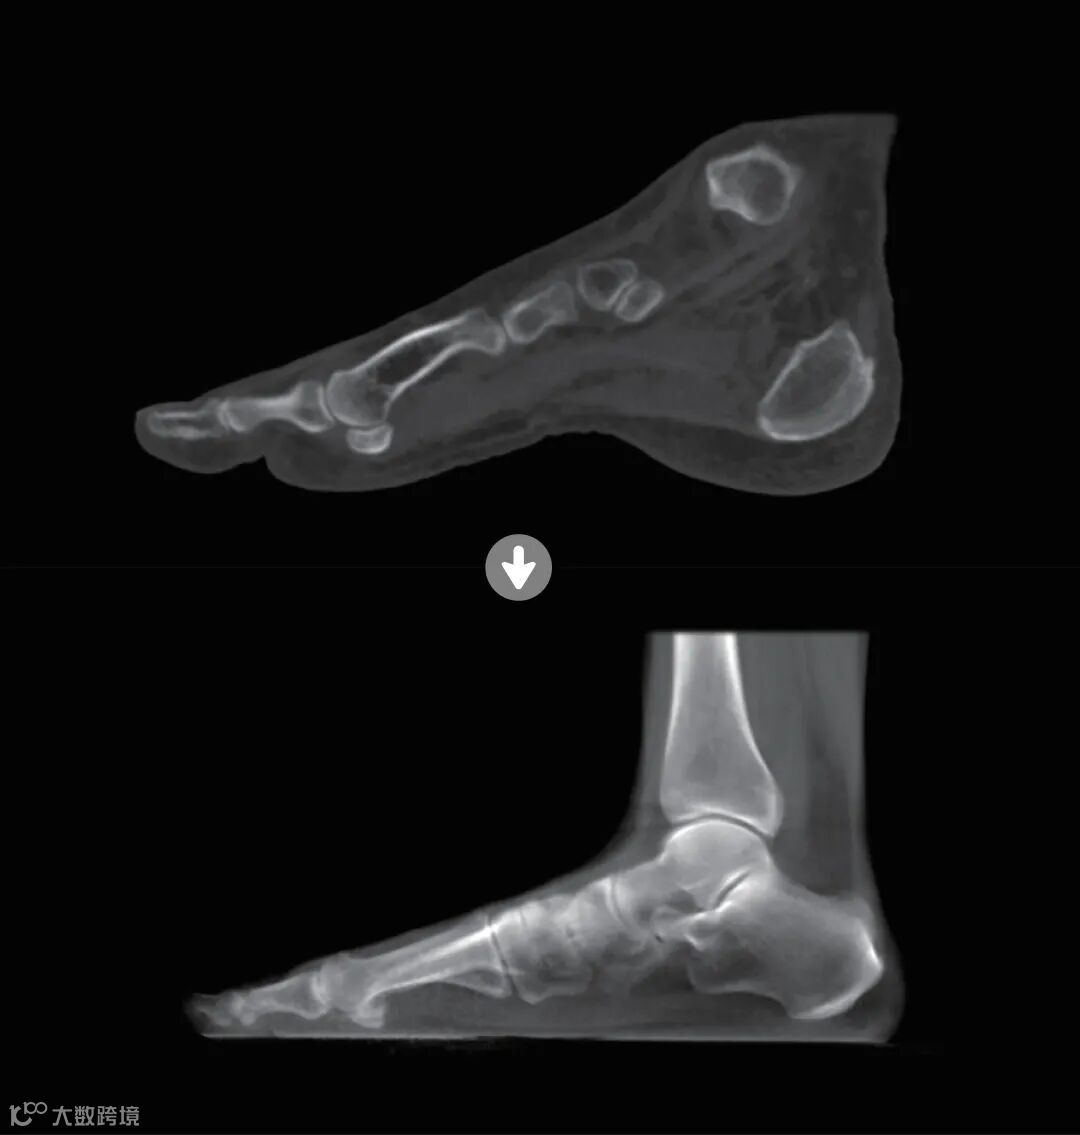

图:从传统CT成像到骨关节CT高清成像

与此同时,赛诺威盛基于站立位CT影像解决方案,有针对性地开发出负重位下的智能全身力线测量和平衡评估应用,能够基于全身CT数据,支持任意区域的处理、重建及查看,让用户能够自由选择感兴趣的区域进行深入分析;该应用兼具了3D与2D测量功能,特别对于重叠性组织,能够提供更为精确的测量结果,真正实现了精准成像,精准测量,为精准诊疗提供了有力支持。

SigmaCT 720 天迹,其先进的整体设计可以支持专科化多部位扫描,包括负重位单双足、膝关节扫描,以及非负重位单双足、手腕扫描;领先的硬件配置可以支持专科化超清骨成像,可识别隐匿性骨折,提高2倍复杂骨折的识别率;并且提供了三种扫描模式,包括平片模式、透视模式以及三维模式,灵活满足不同的临床使用场景。